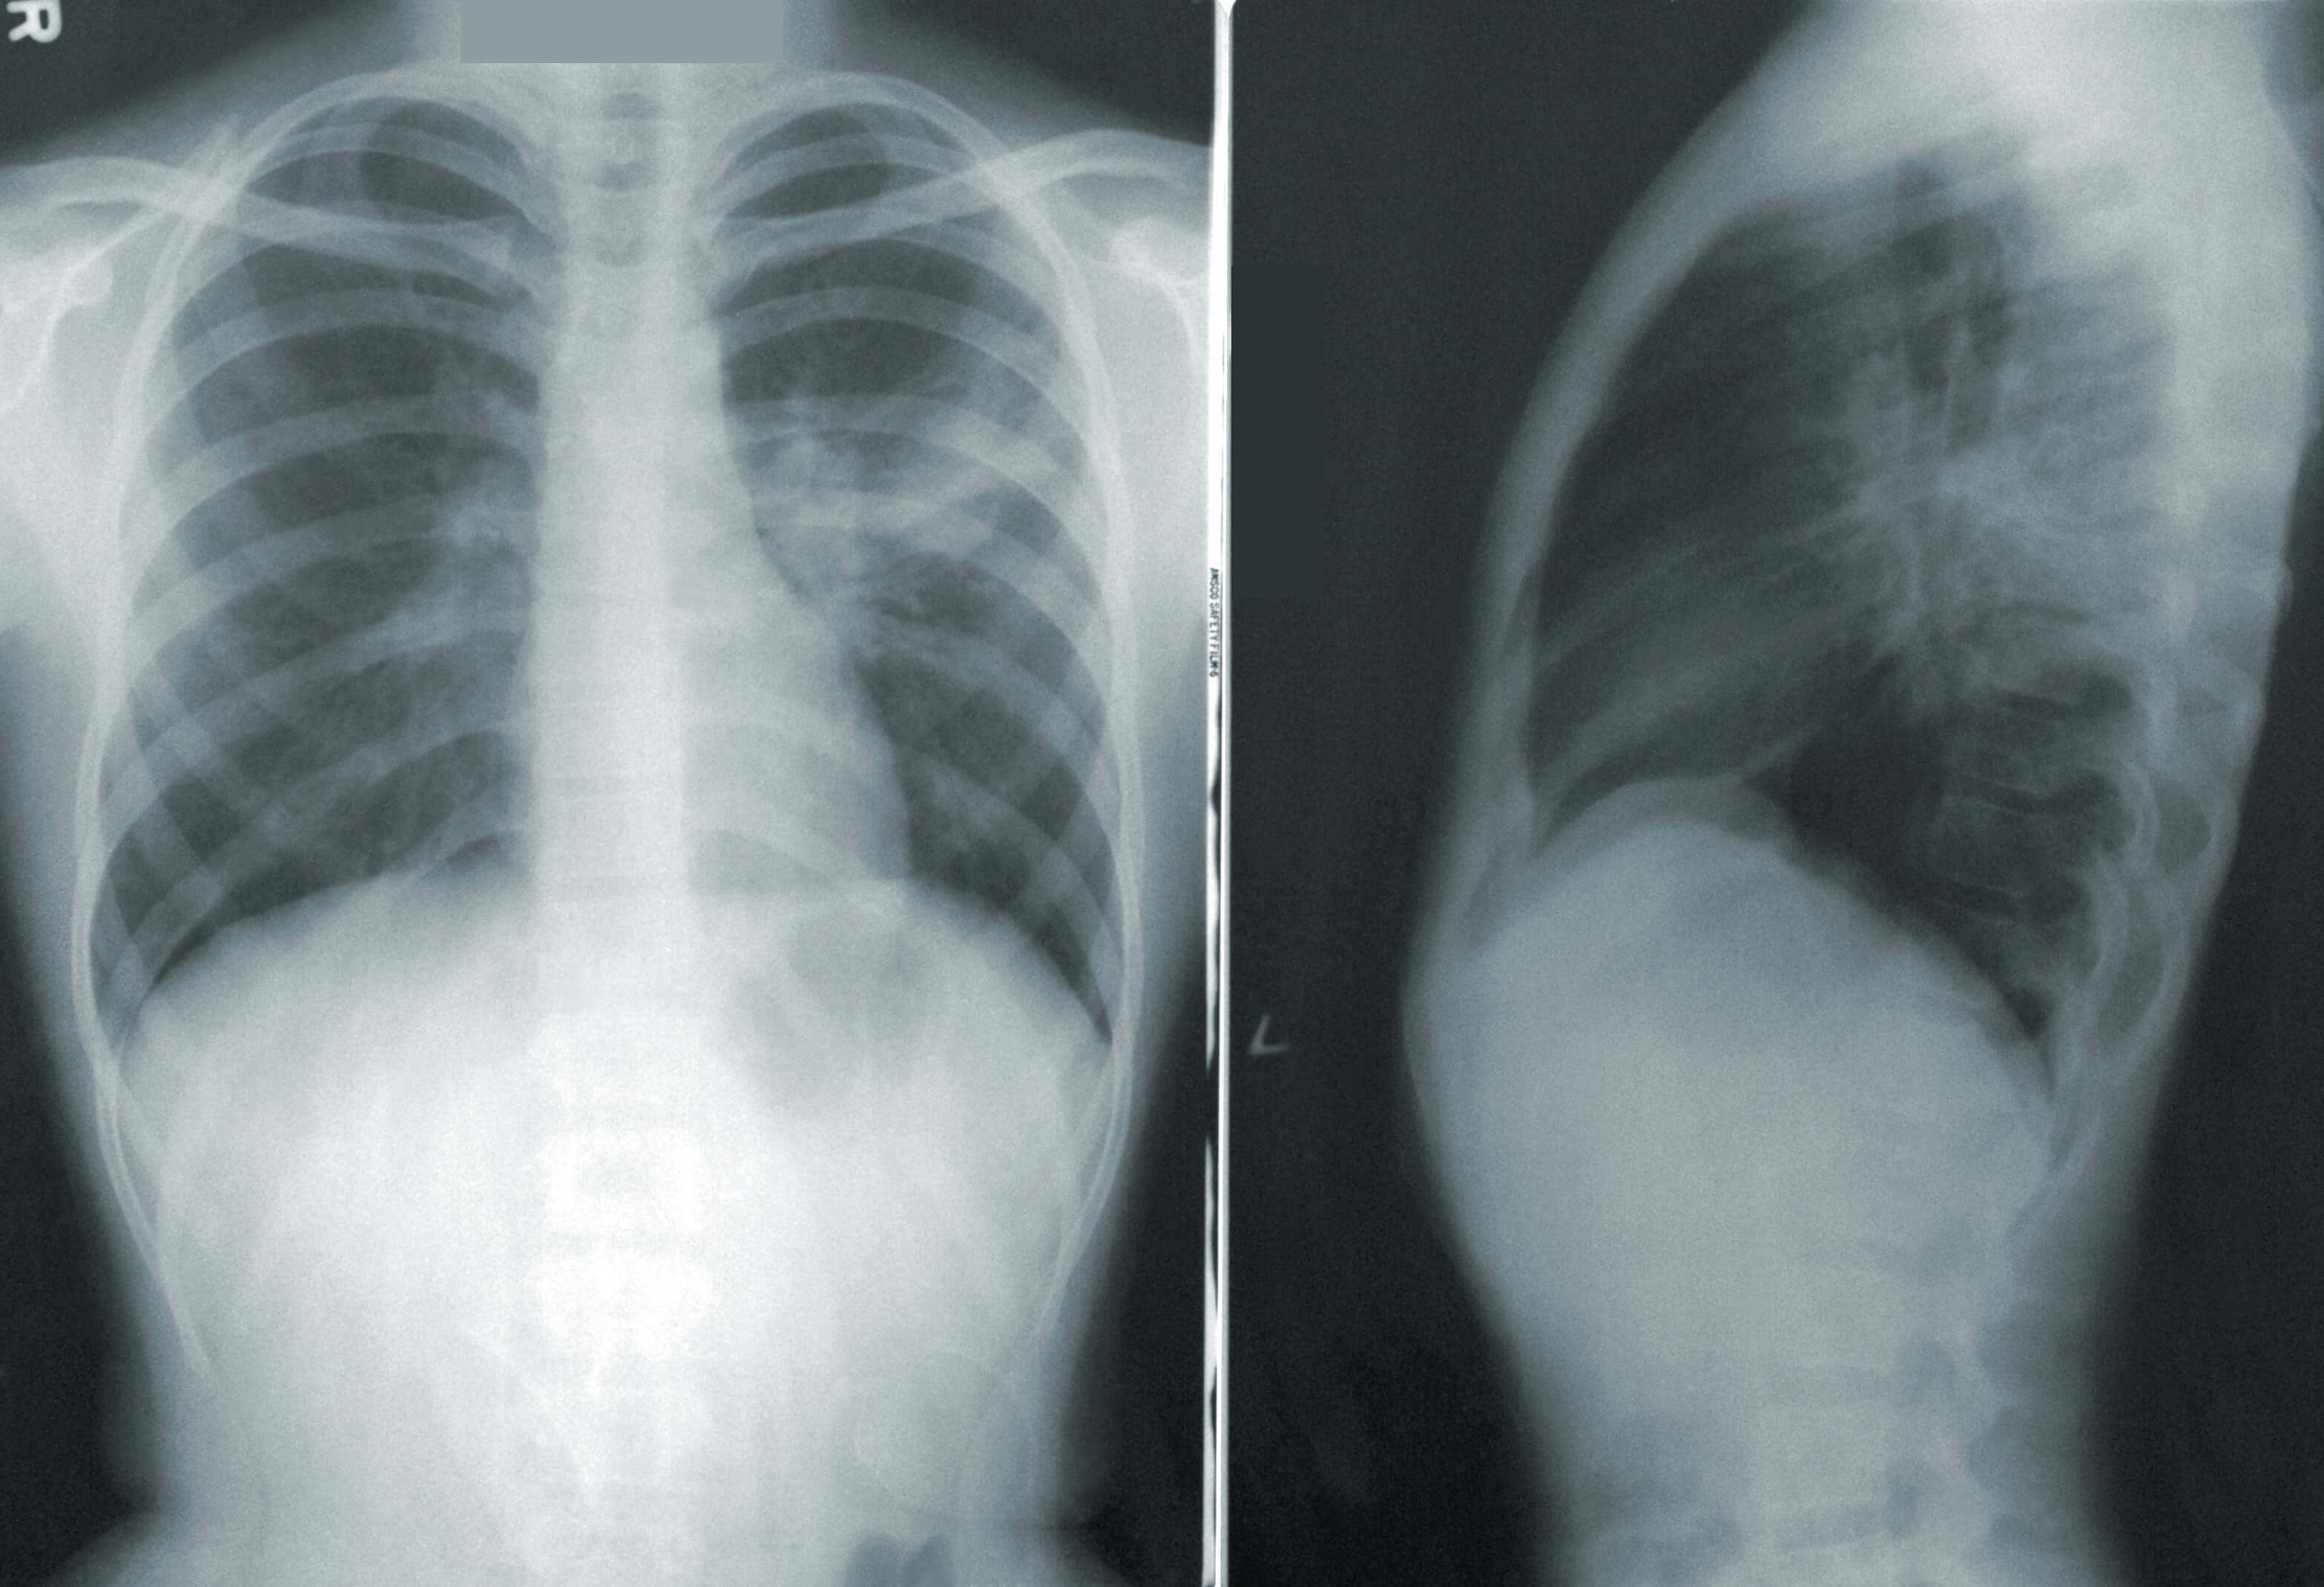

3. 숨이 차고 호흡이 어려워짐(호흡곤란) 😮💨

폐암이 진행되면서 폐 기능이 저하되면 숨이 차는 증상이 나타날 수 있습니다.

초기에는 계단을 오르거나 운동할 때만 가볍게 숨이 차는 느낌이 들지만, 병이 진행될수록 가벼운 활동이나 휴식 중에도 숨이 가빠질 수 있습니다.

평소에 문제가 없던 사람이 갑자기 가벼운 움직임에도 호흡이 힘들어진다면, 폐 내부에서 산소 교환에 장애가 생겼을 가능성이 큽니다.

이는 암세포가 기관지를 막거나, 폐 조직이 손상되면서 폐활량이 줄어들기 때문에 발생하는 것입니다.